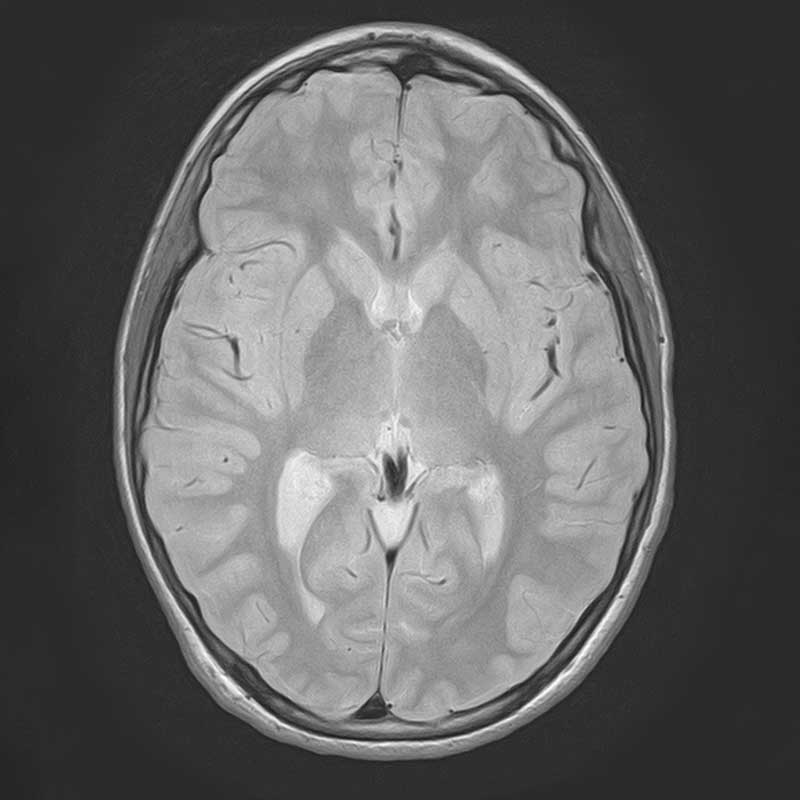

. Ein MRT-Scan eines menschlichen Gehirns, axialer Schnitt, zeigt Strukturen und Gewebe.

T2-gewichtete HR Sequenz des Neurokraniums

. Dies ist ein MRT-Bild eines menschlichen Gehirns in horizontaler Ansicht.

Protonen-gewichtete Sequenz des Neurokraniums

Um Erkrankungen des Gehirns und der Wirbelsäule zu diagnostizieren, sind modernste Technik (MRT, CT) und ein hohes Maß an Spezialisierung erforderlich. Unsere Neuroradiologie setzt modernste Großgeräte für die Bildgebung des Zentralnervensystems (ZNS). Software- und Hardwareentwicklungen erlauben es, Hirnstoffwechsel und Hirndurchblutung optimal darzustellen. Wir haben uns daneben auf die neuroradiologische Diagnostik degenerativer, traumatischer und entzündlicher Gehirn- und Rückenmarksfragestellungen spezialisiert. Dabei kooperieren wir mit dem Asklepios Fachklinikum Göttingen bei psychiatrisch-neurologischer MRT-Bildgebung. Diagnostik und minimalinvasiver Therapie degenerativer Wirbelsäulenerkrankungen ist Teil unseres Wirbelsäulenzentrums.